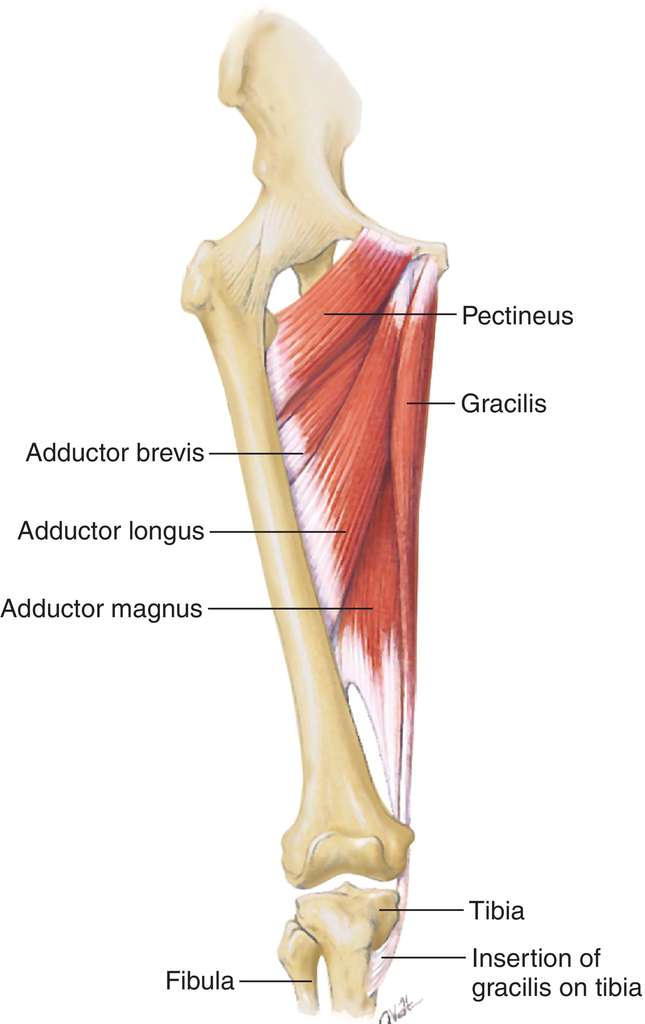

Анатомия и Функции Мышцы Adductor Magnus